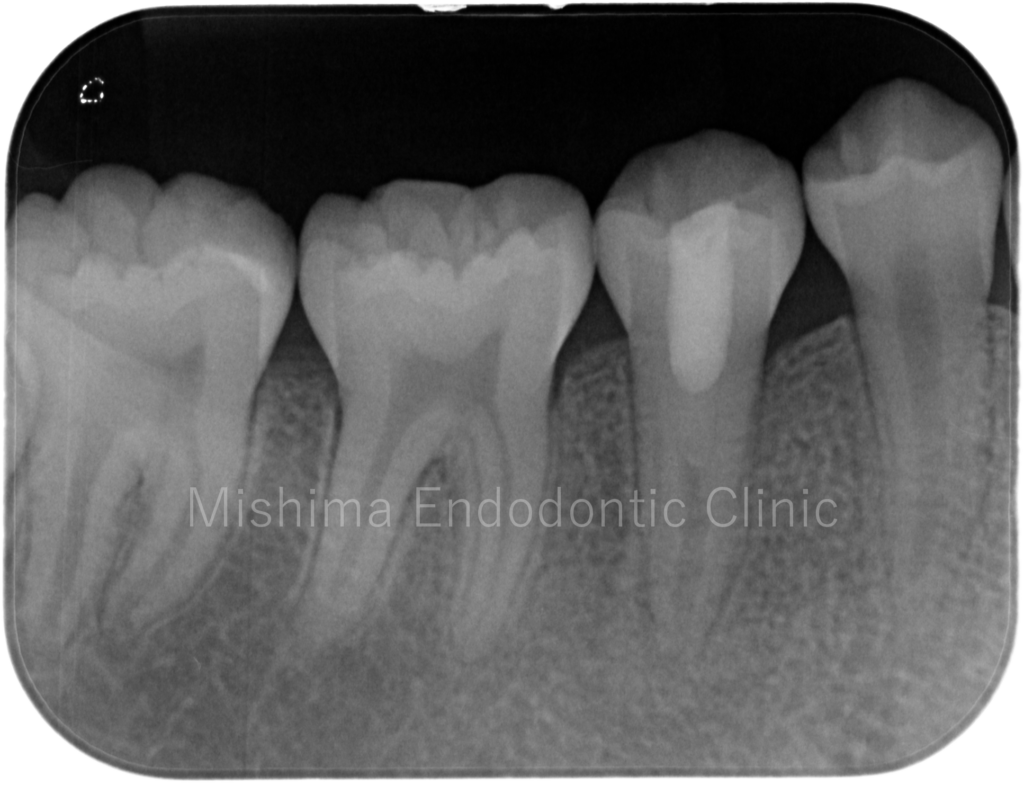

Before

After

| 治療内容 | 歯髄診査にて電気歯髄診、coldテストにて陰性反応を示し、歯髄壊死と診断。患者は12才歯は根未完成歯であることから、再生歯内療法を行った。術後、電気歯髄診、coldテストに て陽性反応を示し、根尖透過像も消失し、経過は良好。 |

術前

術直後

術後7カ月

再生歯内療法後、7カ月後の様子です。

術後11ヶ月